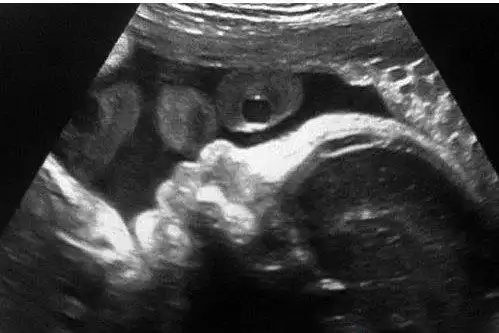

夏奇拉挺大肚晒b超宝宝照 欲在巴塞罗那建新居